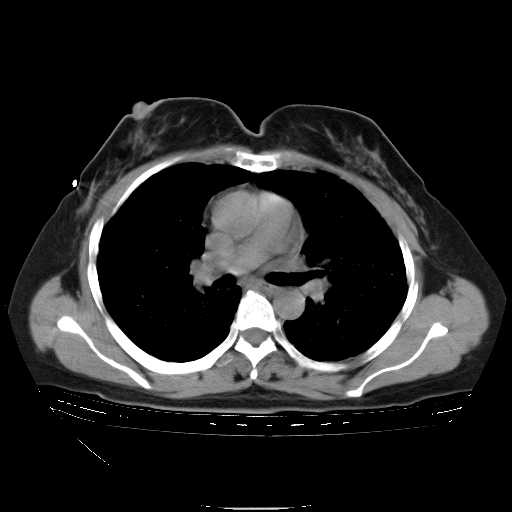

下面是今天刚刚做的,在上海治疗,吃了家属也说不清的一种药,一个月1万左右,

考虑  腺癌肺内转移,治疗较前病灶缩小、减少

肺癌并肺内转移,这种疾病治疗后在影像上看略有好转,不是很显著,但是肿瘤治疗效果影像只是一方面。

支持肺癌并肺内淋巴管炎,  原发灶小了,但转移较前片明显了.

支持右肺下叶周围型肺癌并肺内淋巴管炎,  原发灶小了,但转移较前片明显了.。

标准的细支气管肺泡癌呀!治疗后病情有所控制,也没治愈的迹象!

支持右肺下叶周围型肺癌并肺内淋巴管炎;病灶有所控制。